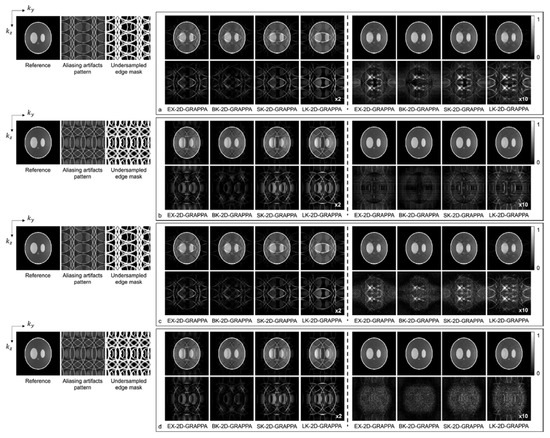

3.2. Computer Simulations

4. Results